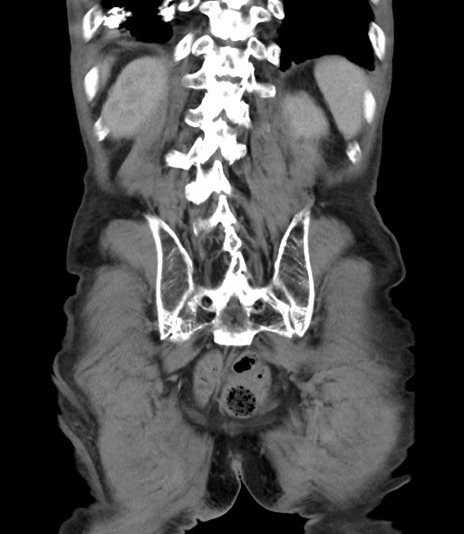

症例3(冠状断像)

症例

【症例】 70歳代男性

【主訴】右鼠径部腫瘤、疼痛

【現病歴】本日朝より上記主訴あり、受診。

【既往歴】膀胱癌にて膀胱全摘、両側尿管皮膚瘻

【データ】WBC 5600、CRP 0.56